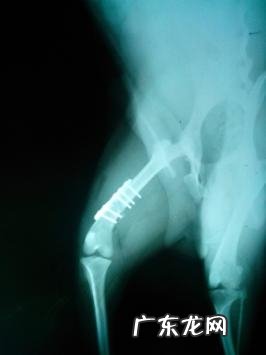

x光图

接骨板内固定不动后的X片图,由此可见骨裂线早已两端对齐

探讨:1.最终一图的X光片能够见到骨裂断端早已两端对齐,基础做到预估的医治的目地 。